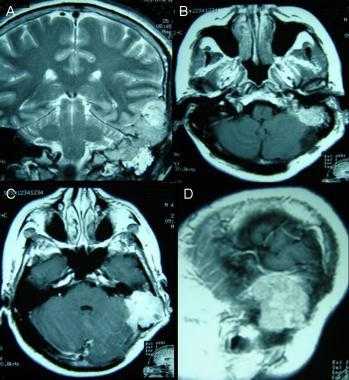

Метастазы головного мозга на МРТ. Фото. Определяются множественные метастазы в мозг при раке легкого: слева в режиме Т1-ВИ в виде гипоинтенсивных образований, справа — в режиме Т2-ВИ виде множественных участков повышенного сигнала, окруженных зоной перифокального отека. У пациента подтверждена первичная опухоль легкого.

Т1 ВИ (без контрастного усиления)

- Изоинтенсивный либо умеренно гипоинтенсивный сигнал по отношению к белому веществу мозга от активной части опухоли

- Гипоинтенсивный сигнал от центральной зоны (некроза и распада)

Т2 ВИ

- Гиперинтенсивный сигнал от центрального участка метастаза

- Повышение интенсивности сигнала от отечных тканей мозга, окружающих вторичную опухоль, вследствие чего метастазы становятся более четкими на изображениях

МРТ с контрастным усилением

- Выраженное увеличение интенсивности сигнала

- Усиление сигнала по периферии в виде «кольца» или «короны»

- Помогает дифференцировать кровоизлияиния в метастаз от геморрагического инсульта (выраженное усиление сигнала на Т1 ВИ)